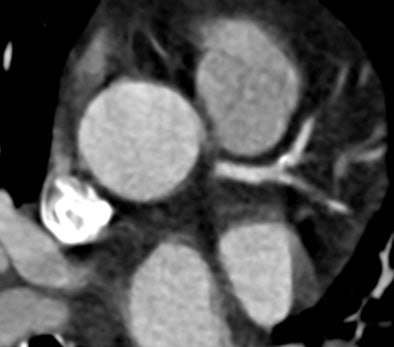

![]() |

| Dual-source CT was able to rule out coronary artery disease in a 31-year-old man with chest pain and an abnormal SPECT exam. A 270-msec scan covered a single diastole at 75-msec temporal resolution with a radiation exposure of less than 1 mSv. All images courtesy of Dr. Joseph Schoepf. |